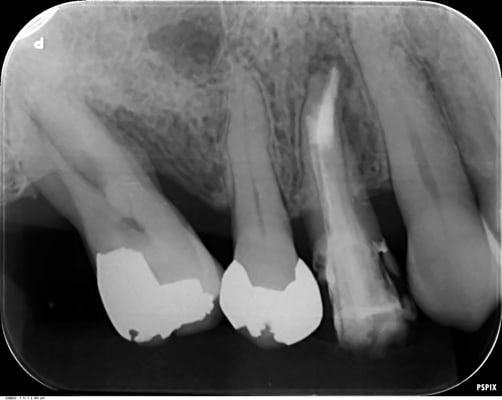

右上7番

根管内には、3本の破折ファイルの残存。それ以外は、多量の軟化象牙質(一部は髄床底穿孔)。根尖病巣の存在。対合歯とのクリアランス少なく、保存するにも補綴するには無理か?と思われましたが、約1年。月に1度。当院から片道2時間半、かけて通っていただき、無事に補綴に至りました。

これから矯正治療になりますので、まだまだ長い道のりです。

1年後

根尖の透過像も消失し、自覚症状(咬合痛などもありません)安心して最終印象採得(型どり)を行いました。

当院では、CTやレントゲンを撮影して悪い像(根尖などのX線透過像)が消失するのを確認してから補綴するようにしています。

透過像が残っているまま、治療を終了させるアメリカ的な合理主義的な考え方には断固として共感できませんね。